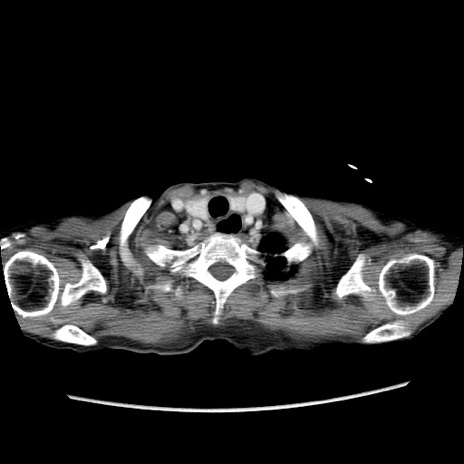

症例25(横断像)

【症例】80歳代女性

【主訴】胸のつかえ感

【現病歴】約9時間前に食後から胸のつかえた感じあり、嘔吐あり、来院。

【既往歴】胃癌(全摘)、胆摘、虫垂炎

【身体所見】心窩部に圧痛あり、反跳痛なし。

【データ】WBC 5700、CRP 0.05